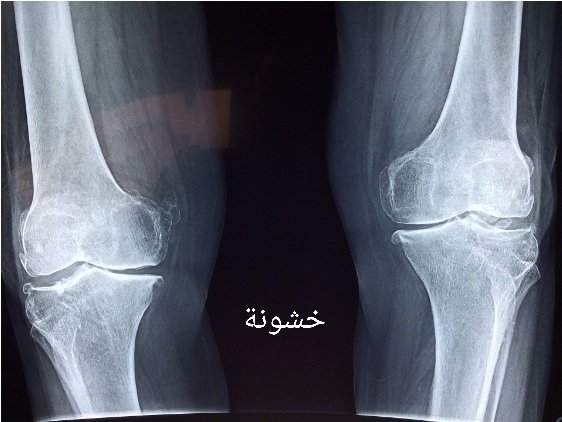

العلاج لخشونة الركبة:

١- يعتمد على درجة الخشونة و عمر المريض.

-الخشونة البسيطة والمتوسطة: الحل تحفظي وغير جراحي أما الخشونة الشديدة يكون الحل جراحي.